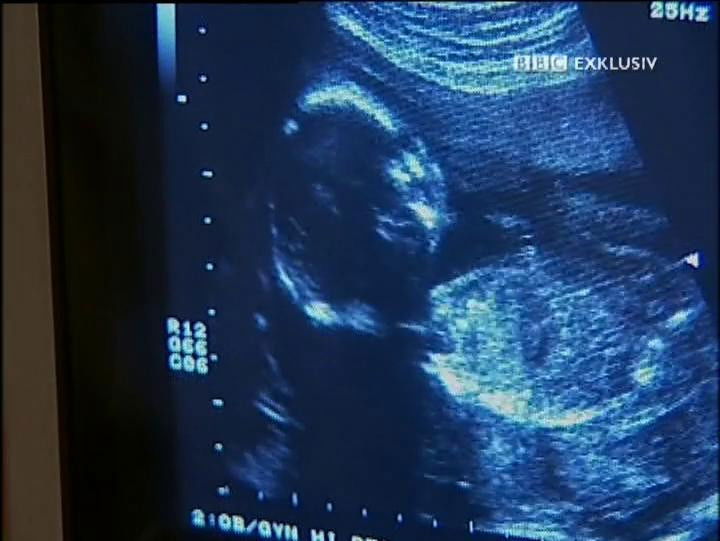

Babies

1 - Babies